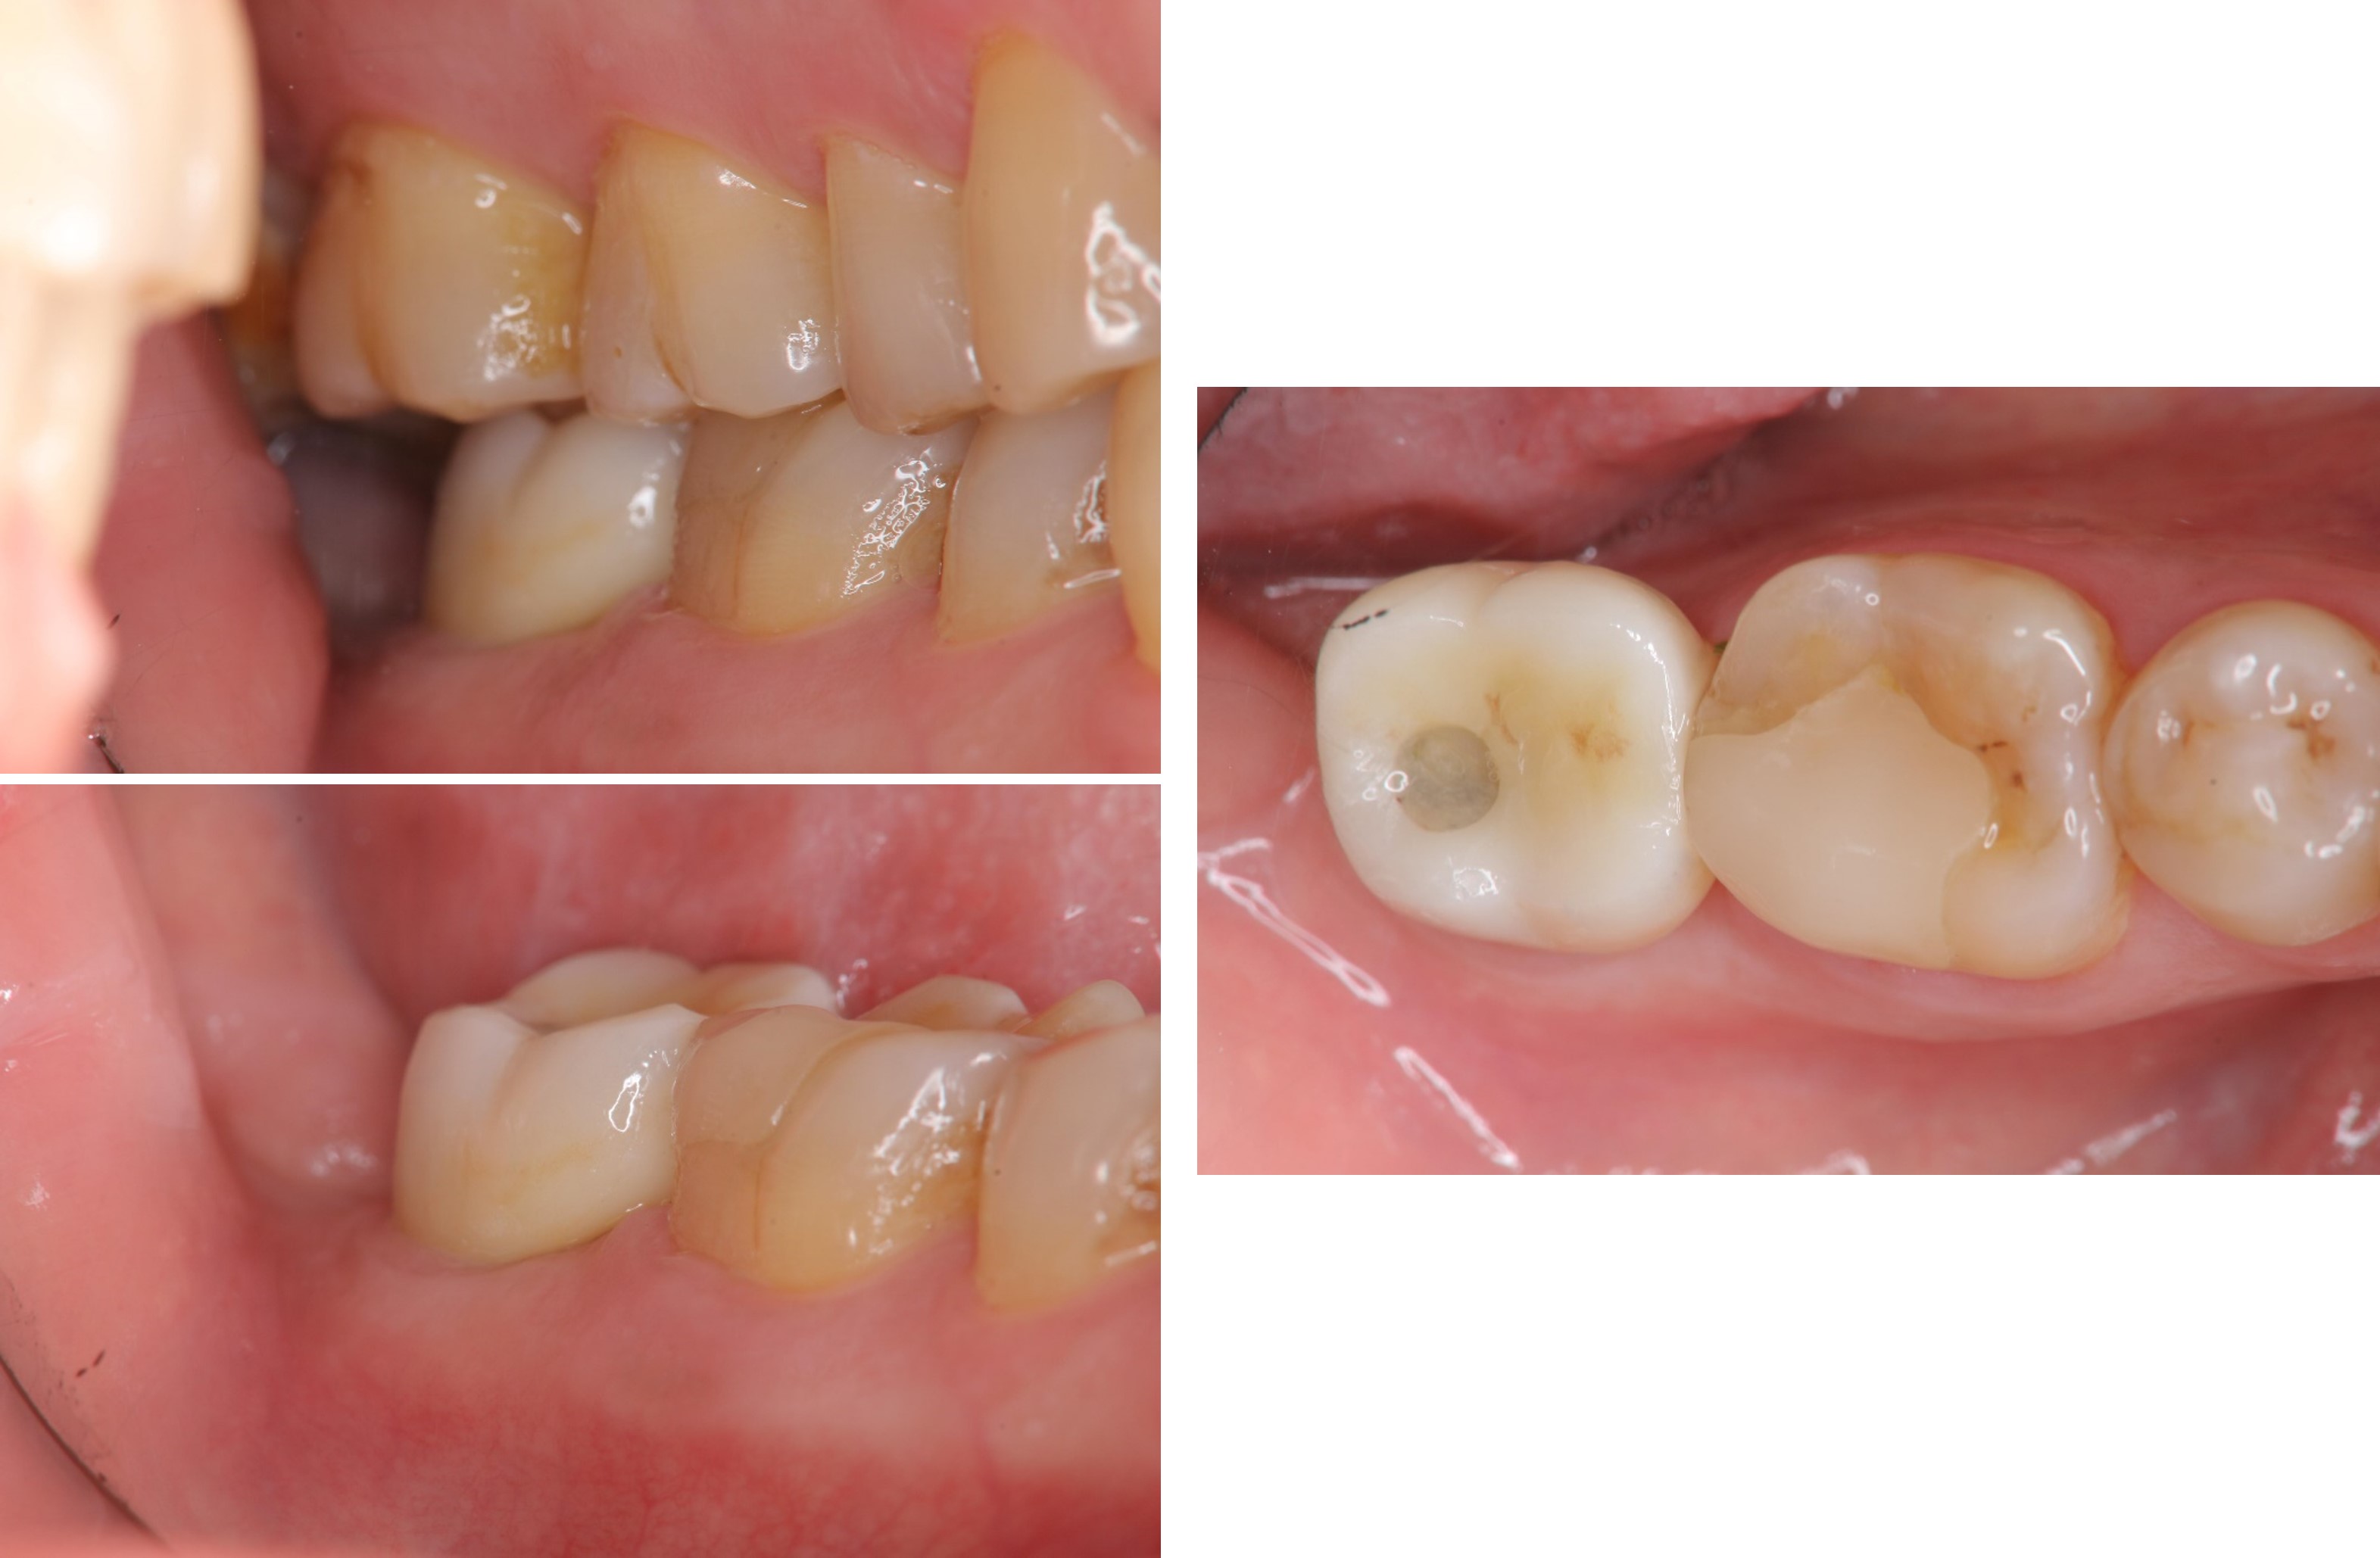

治療前,二次蛀牙,咬頭受損

當蛀牙破壞程度大

陶瓷冠塊體是根據蛀牙的窩洞量身訂做,不管是顏色、精密度都是最佳的選擇,因此是非常美觀與持久的填補窩洞材料與技術